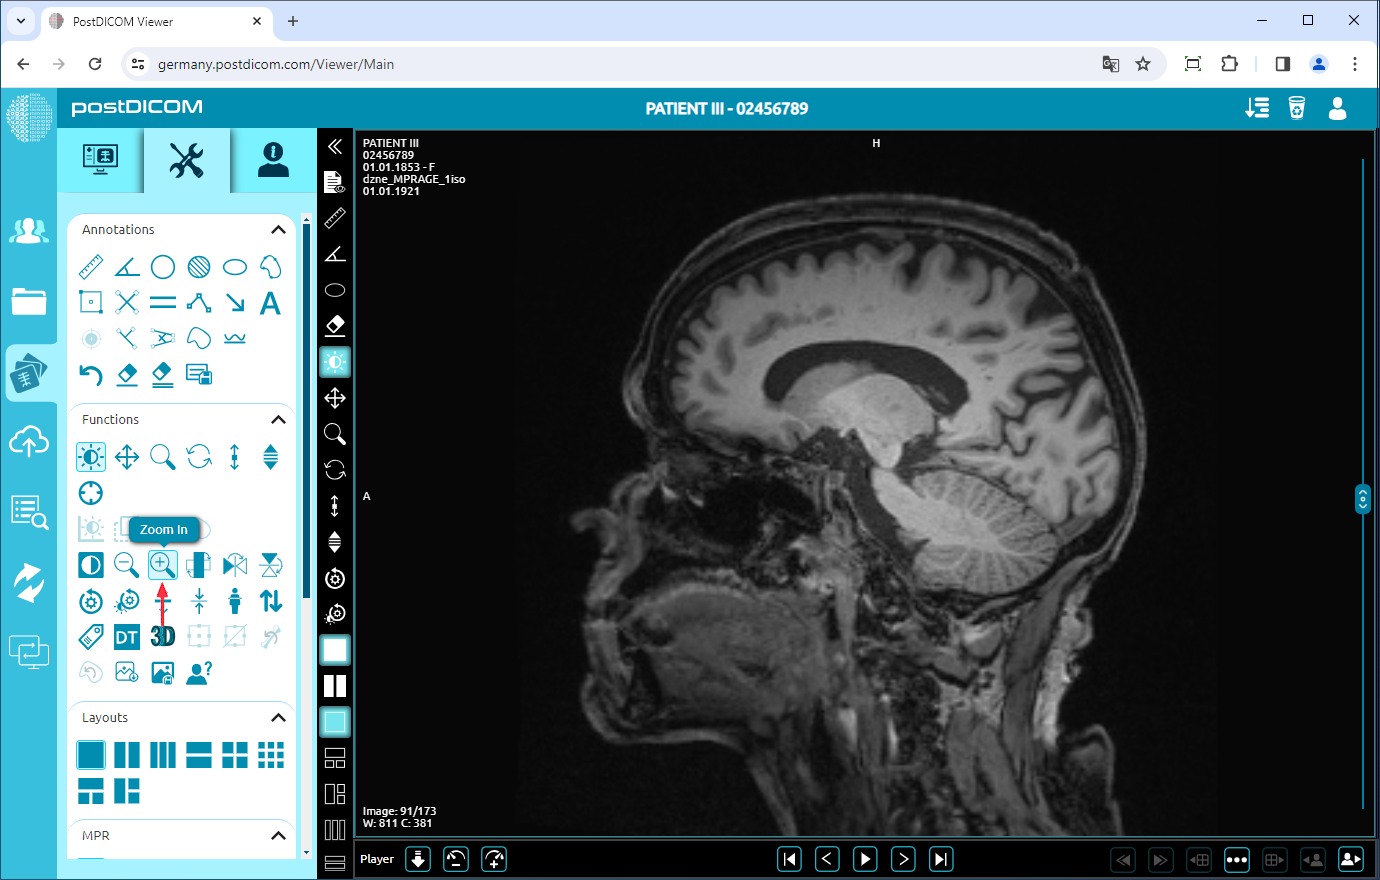

Zoom In/Out

Click on the “Zoom In” icon on the left side of the page to zoom in on the image by one level.

After clicking, the image will be one level bigger. The more you click, the image will be bigger.

To zoom out the image by one level, click on “Zoom Out” icon on the left side of the page.

After clicking, you will see that the image will be one level smaller. The more you click, the image will be smaller.